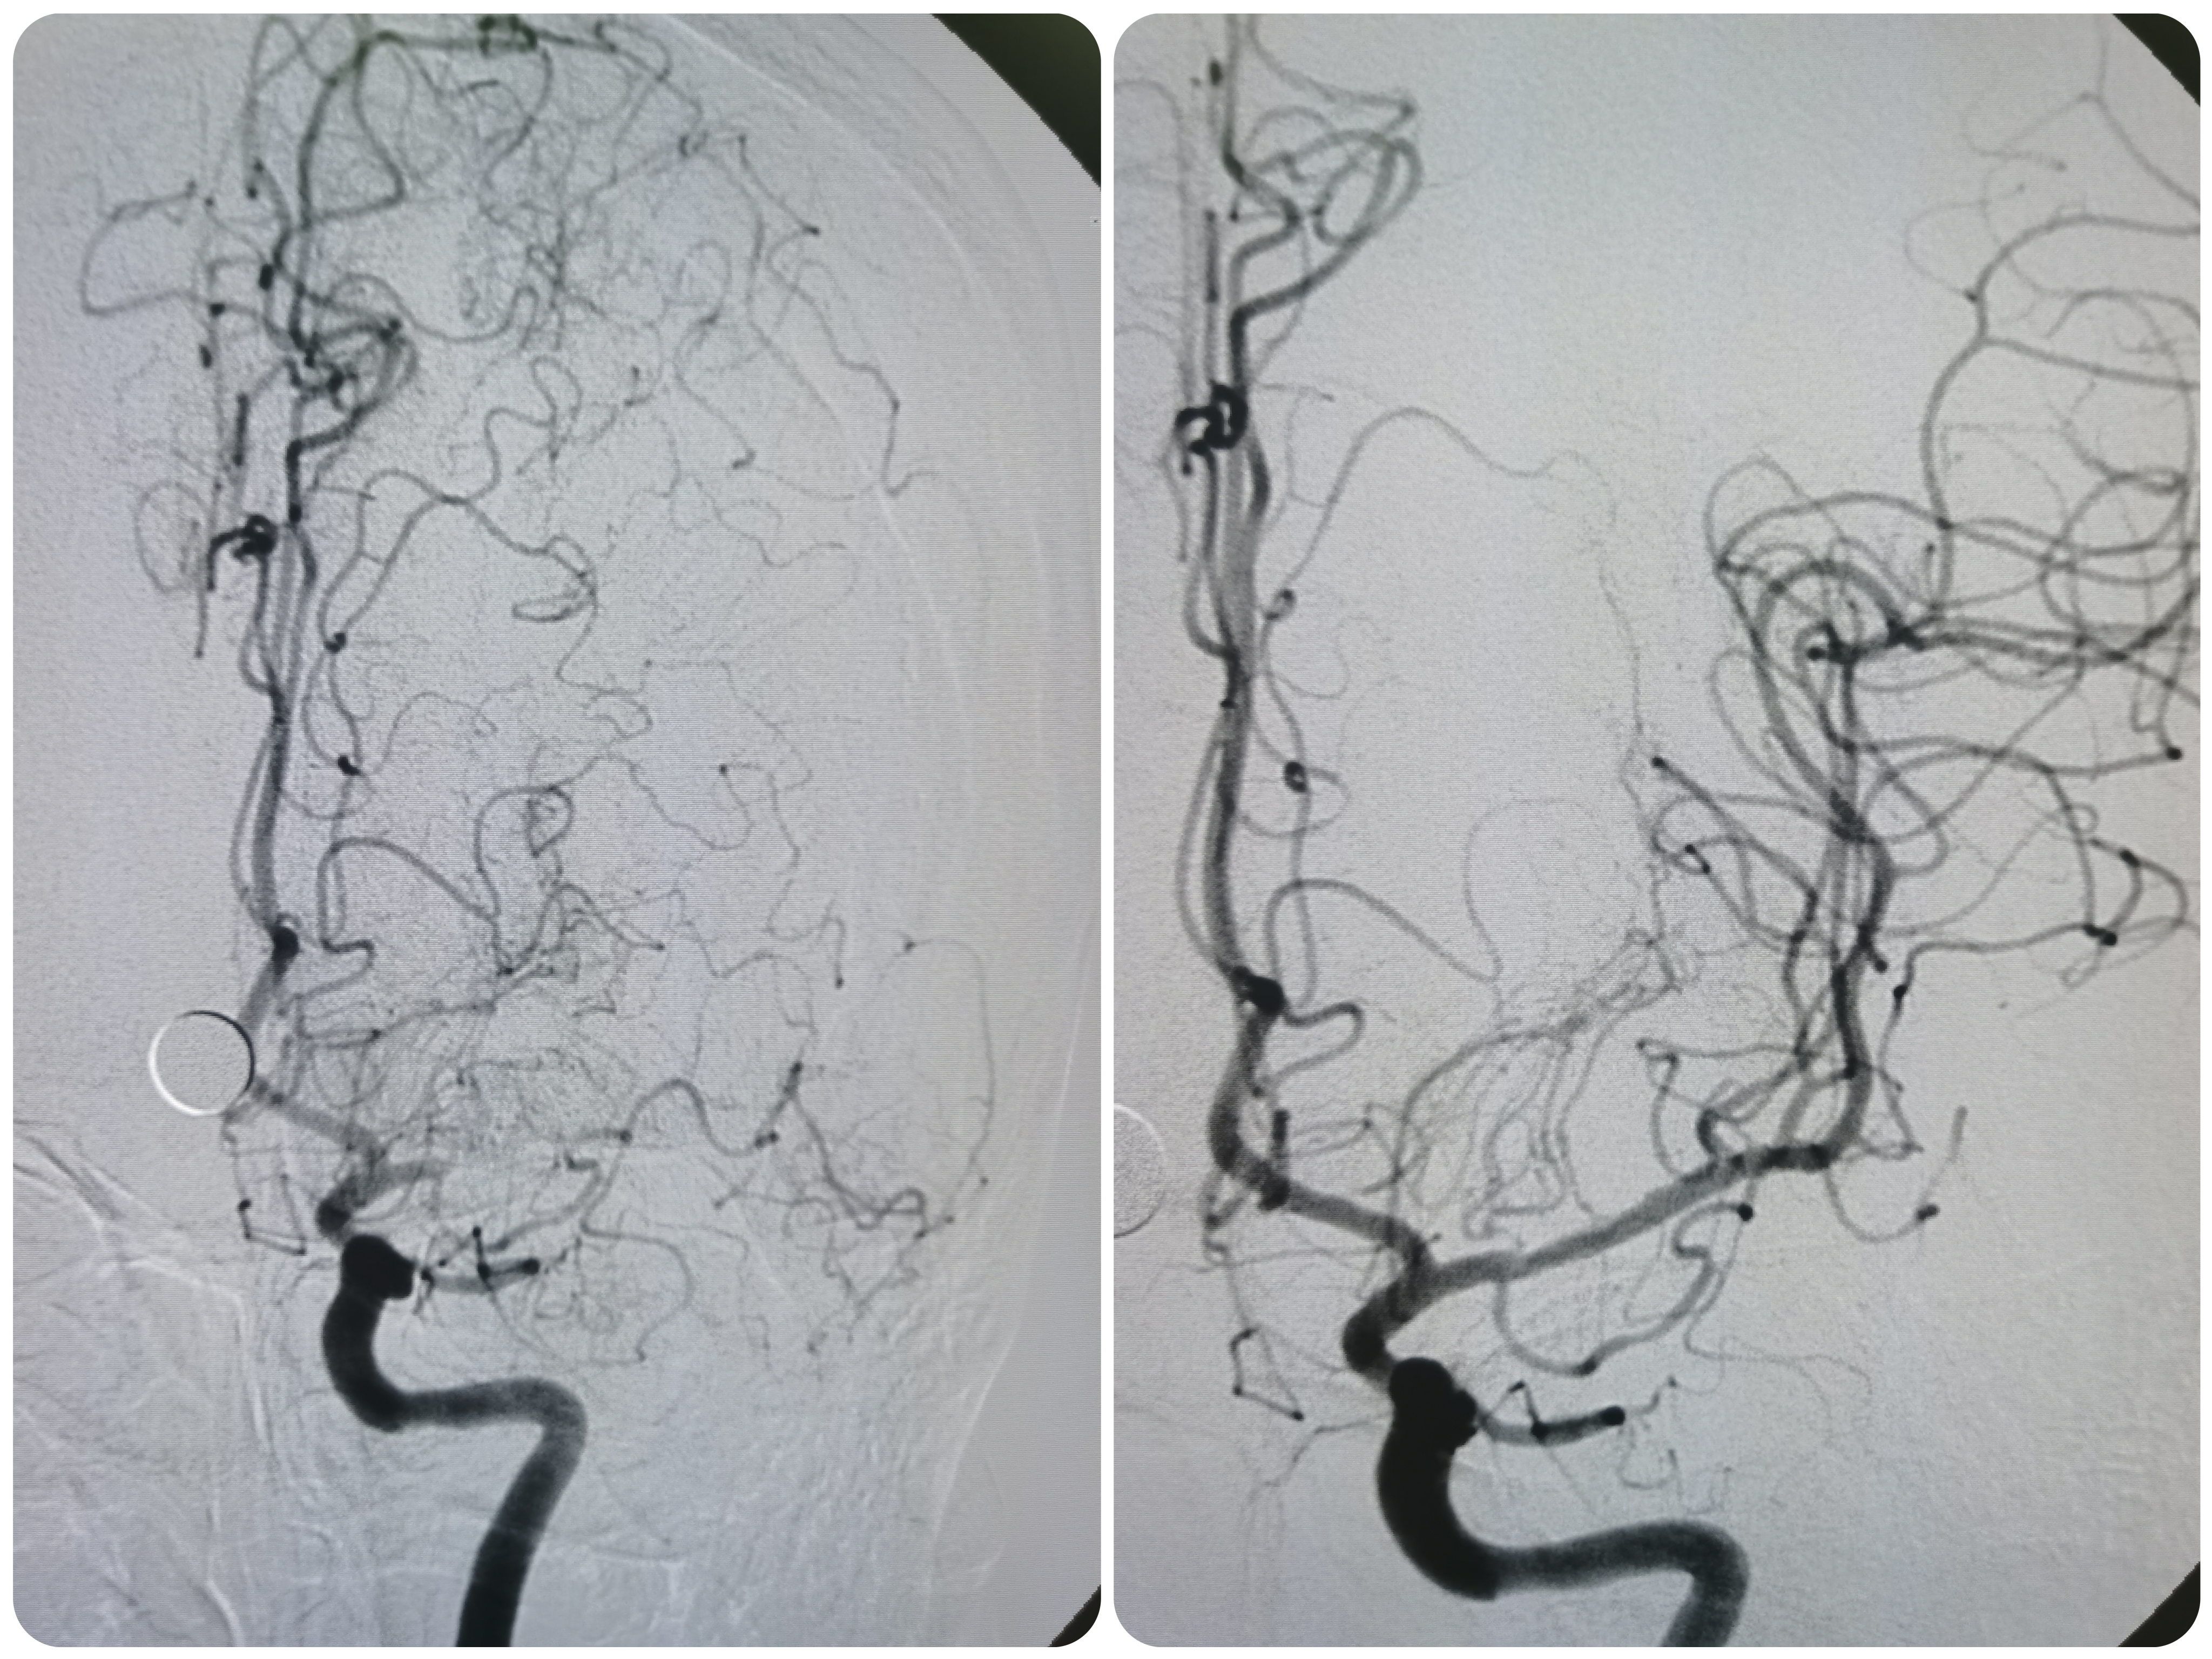

全麻后,将8F导引导管及中间导管顺利到位,建立路径,在路径图下微导丝携微导管顺利通过病变。

微导管确认位于真腔,交换入Transend300导丝。

2.0/15球囊扩张闭塞处。

扩张后造影见近端显影,远端血管仍闭塞。

将球囊前送,再次加压扩张。

扩张后造影见血管再通,血流通畅。

侧位造影见血流通畅。

观察15分钟后造影血流通畅,未见夹层及明显弹性回缩。